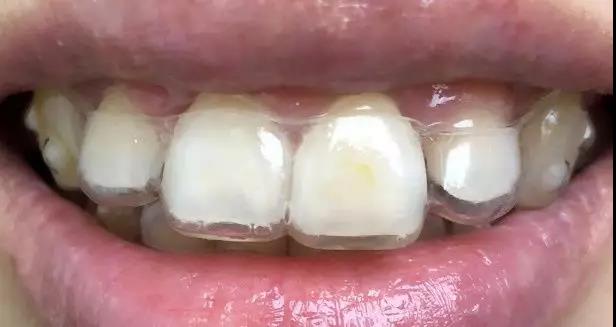

1.活动矫治器

微信图片_20200210130915

疫情期间注意事项:

(1)用清水清洗矫治器,必要时可用酒精棉片对矫治器进行擦洗消毒;

(2)取戴矫治器前做好手卫生;

(3)按照医生要求佩戴,切勿遗失;

(4)因为疫情短期无法复诊:与主治医生取得联系,必要时拍摄照片图文咨询。

紧急情况处理方法:

(1)矫治器损坏,丢失,固位不良:暂不佩戴矫治器,联系主治医师预约复诊处理。

(2)钢丝折断脱落:不影响就位可继续佩戴;若就位不良可暂不佩戴矫治器等待下次复诊。

(3)矫治器基托损坏:不影响就位可继续佩戴,如边缘磨嘴可用指甲刀等工具修剪后戴入,如损坏严重或无法就位则暂不佩戴等待下次复诊。

(4)佩戴前牵引或扩弓矫治器需自行加力:按照医生规定牵引与加力,若到复诊时间无法就诊需咨询自己的主治医生是否继续加力。